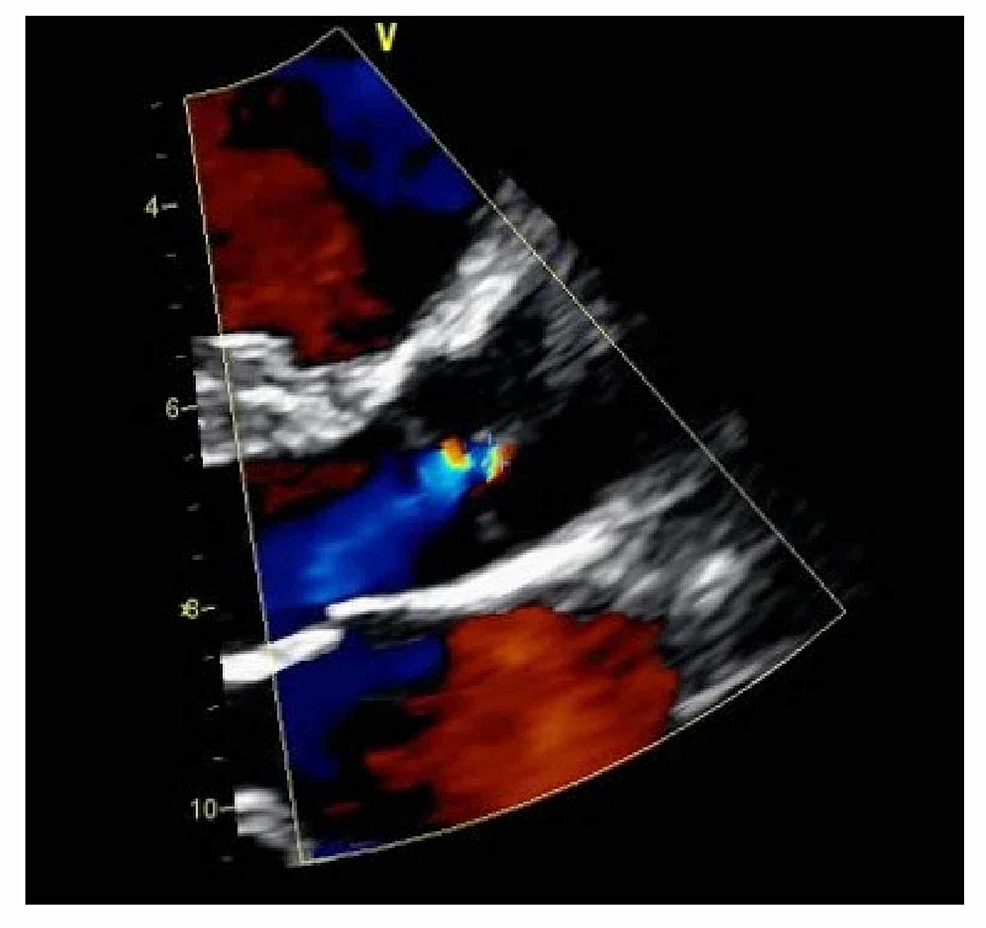

A 29-year-old female in her 37th week of pregnancy was referred to the cardiology clinic for palpitations that started about one to two weeks before presentation. She described the palpitations as intermittent in nature, without any dyspnea, chest pain, or other associated symptoms. Medical history was neither significant for a prior history of medical diseases nor a family history of heart disease. Vital signs were recorded as a heart rate of 80 bpm, blood pressure of 99/61 mmHg, and respiratory rate of 14 per minute. On exam, there was a regular heart rate with normal S1 and S2 without any extra heart sounds. EKG showed normal sinus rhythm. Transthoracic echocardiogram showed normal left and right ventricular size and systolic function, a quadricuspid aortic valve with three equal-sized cusps, and one smaller cusp (Figure 1) and mild aortic regurgitation (Figure 2). No other structural abnormalities were noted. She was advised to follow up at intervals of four to six weeks at the outpatient cardiology clinic for an assessment of volume status and aortic regurgitation. She underwent an uneventful vaginal delivery without any peri- or postpartum complications and was discharged home after three days of hospitalization. Ongoing follow-up with a cardiologist was recommended to monitor the post-partum complications of QAV in the setting of aortic regurgitation.